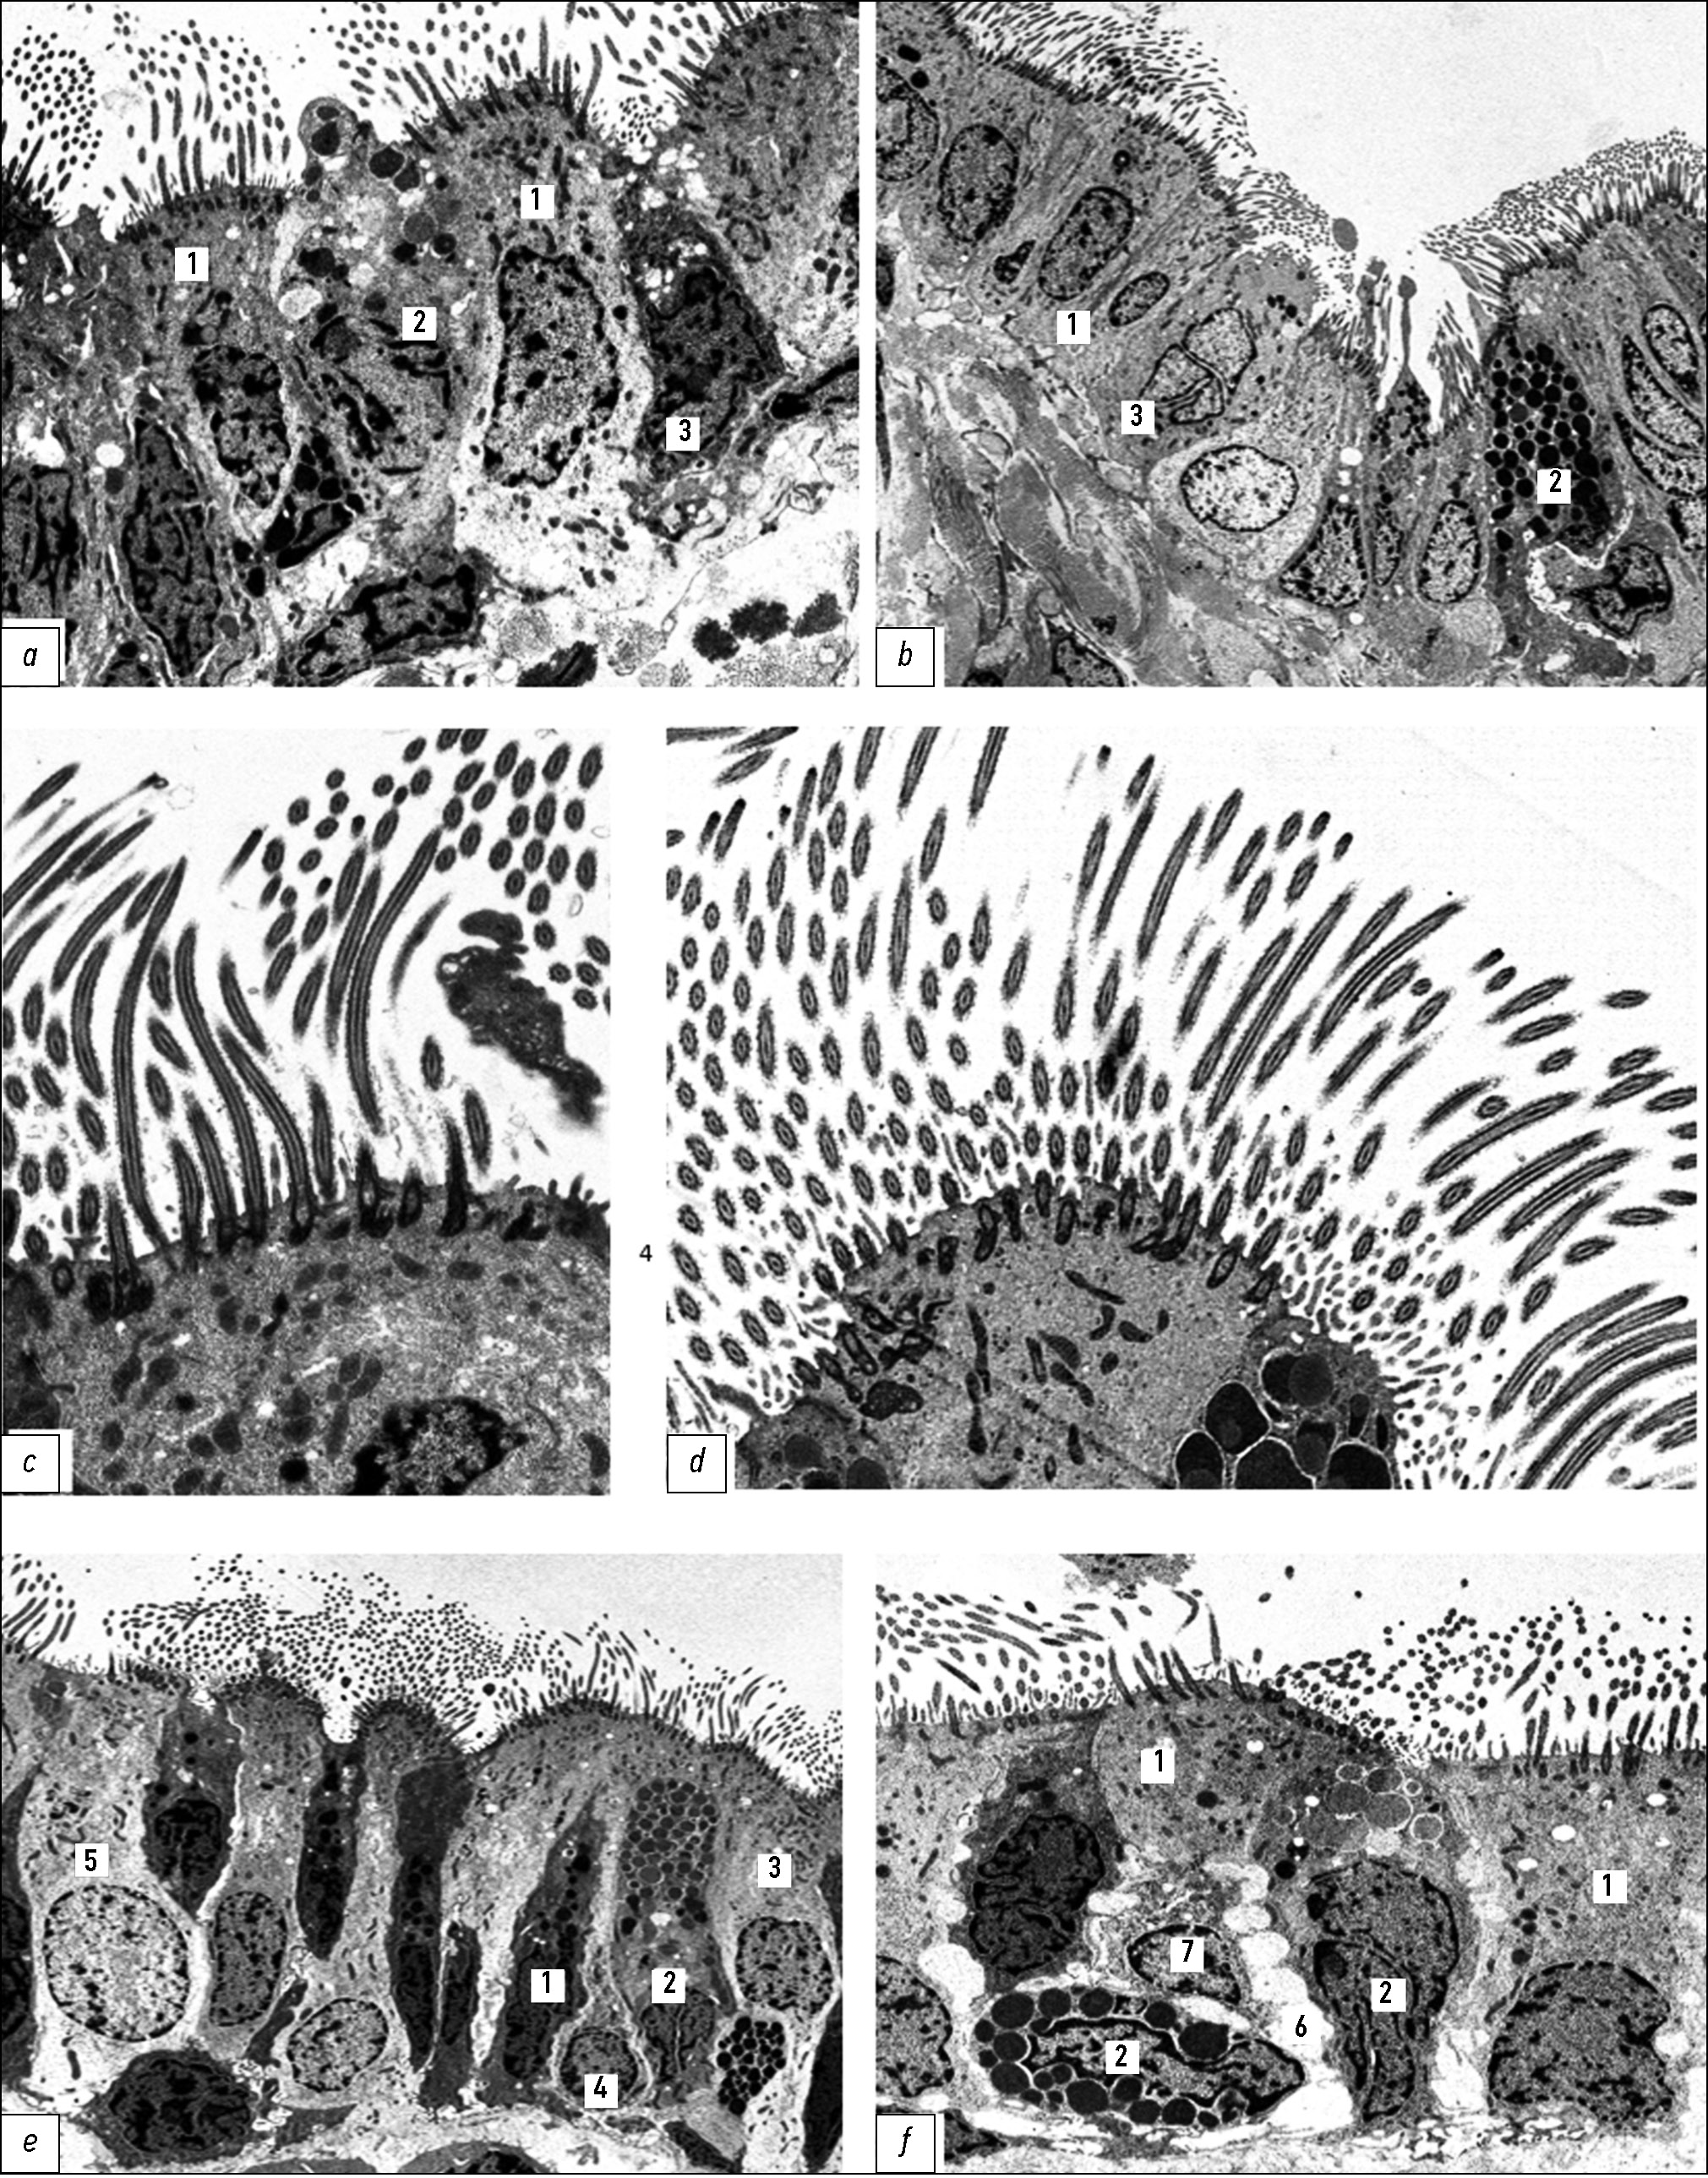

Бронхиальное дерево новорождённых крыс во всех отделах выстлано однослойным эпителием, состоящим преимущественно из недифференцированных (промежуточных) клеток, реснитчатые клетки встречаются в небольшом количестве (рис. 1, a–c). В течение двух недель после рождения доля реснитчатых клеток в эпителиальном пласте значительно увеличивается в результате активных процессов дифференцировки (цилиогенеза). Одновременно пропорционально снижается содержание малодифференцированных элементов. На апикальных полюсах дифференцирующихся реснитчатых клеток можно наблюдать разные этапы формирования ресничек (рис. 1, d, e). Созревание реснитчатых клеток происходит группами, это отчётливо видно при сканирующей электронной микроскопии (рис. 1, f). Типичная структура многорядного мерцательного эпителия формируется к концу первого месяца после рождения.

Рис. 1. Эпителиальная выстилка бронхов крыс: а — главного бронха, b — долевого бронха, c–e — сегментарных бронхов у новорождённых; f — сегментарного бронха у крыс в возрасте 8 суток. 1 — реснитчатые, 2 — щёточные (безреснитчатые), 3 — базальные клетки. Трансмиссионная электронная микроскопия, а–c — увеличение ×5000, d, e — ×8000; f — сканирующая электронная микроскопия, увеличение ×4500.

Fig. 1. Bronchial epithelial lining in rats: a, main bronchus; b, lobar bronchus; c–e, segmental bronchi in newborns; f, segmental bronchus in 8-day-old rats. 1, ciliated cells; 2, brush (non-ciliated) cells; 3, basal cells. Transmission electron microscopy: a–c, ×5000; d, e, ×8000; f, scanning electron microscopy, ×4500.